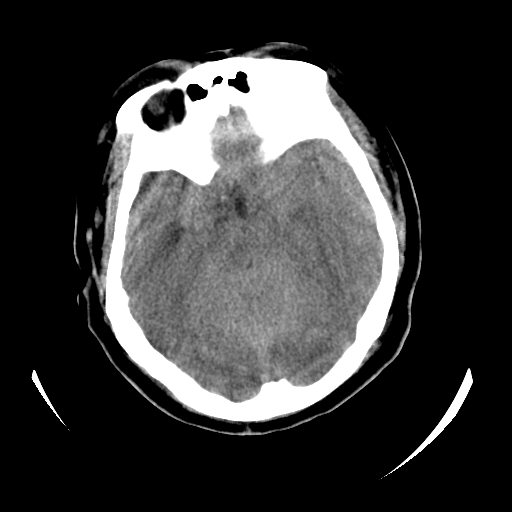

女,53岁,发现昏迷1天,血压不高,有精神病史。临床诊断:脑梗死?

ct诊断:1、双侧基底节区对称性脑梗塞。

2、双侧额叶、枕叶广泛密度减低,考虑缺血梗塞可能性大。

3、脑池小,脑沟浅,提示颅内高压。

测左枕叶白质ct值 约22hu 。请各位老师给出恬当诊断。

征象:病变呈对称性分布于双侧大脑半球,累及范围广泛,白质较灰质密度减低更为明显;脑沟变浅,脑池变窄;

支持3楼老师的分析,颅内广泛性 对称性低密度改变,特别是双侧基底节区的病灶,首先应考虑:缺氧性脑梗死。